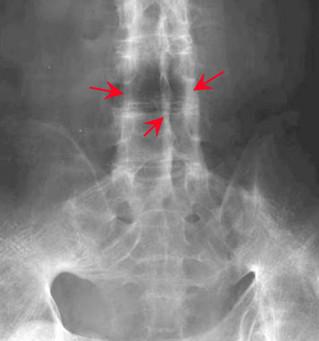

强直性脊柱炎检查影像

2.X线:此项检查也是比较重要的,尤其是患者会出现关节间隙模糊和骨质糜烂的症状,甚至还会有骨密度增高及关节融合。一般说来通常的X线片骶髂关节炎的病变程度分为5级,具体的检查还要根据患者当时的病情来做决定,不同的患者检查的依据标准也是有所区别的,因人而异是诊断的一个非常重要的原则!